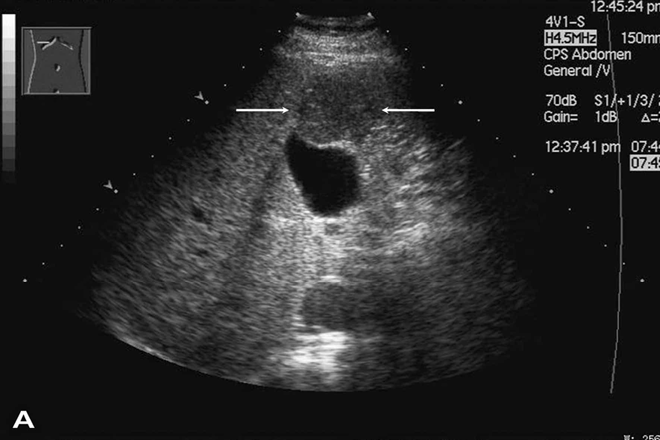

Detección significativa de enfermedad hepática crónica, utilizando 3 simples parámetros de ultrasonido Tres parámetros de ultrasonido tienen una precisión significativa para el diagnóstico de fibrosis severa, con un valor predictivo positivo del 32%. Esta puede ser una forma sencilla de identificar pacientes con enfermedad hepática crónica no diagnosticada. Objetivo La